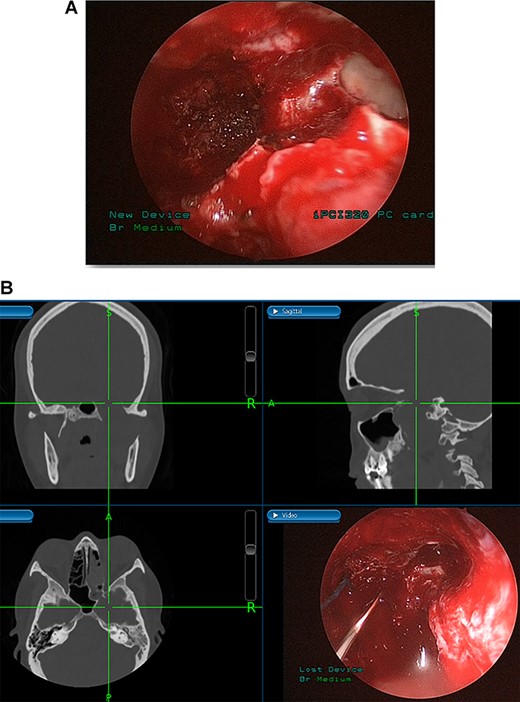

(A) Image-guided tumor removal from petrous carotid artery. (B) Image-guided intraoperative picture status post-complete tumor removal from trigeminal and middle cranial fossa.

(A) Endoscopic view of the final surgical cavity after tumor removal. (B) Image-guided tumor removal from cavernous carotid artery.

The patient underwent an image-guided endonasal endoscopic tumor removal starting by endoscopic medial and posterior walls maxillectomies to control the tumor removal from the lateral sphenoid sinus and the infratemporal fossa after cauterization of the maxillary artery and sphenopalatine artery branches feeding the tumor. The tumor was dissected and removed from the cavernous (Fig. 3A) and petrous carotid artery in the middle cranial fossa (Fig. 3B). The middle cranial fossa’s dura was intact during the tumor removal (Fig. 3C). All the steps of tumor removal were controlled and monitored under image-guided navigation for accurate localization of tumor removal and avoidance of violation to the middle cranial fossa’s dura, or the brain, and the internal carotid artery in its cavernous and petrous segments (Fig. 4a and b).